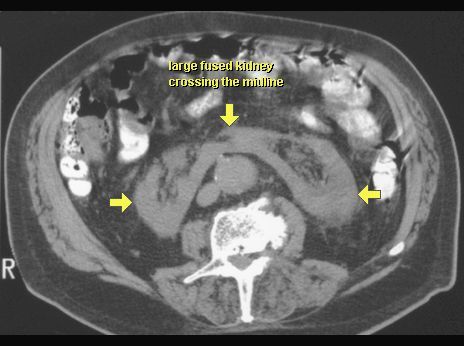

NERKA PODKOWIASTA

TK